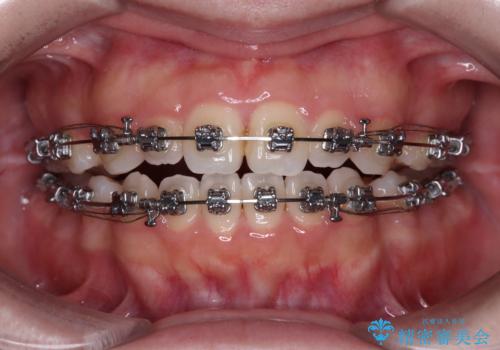

- メタルブラケット

- 1年9ヶ月

舌の突出癖により上下前歯は接触できず、更には前方に押し出されて出っ歯になっている状態でした。

上下左右の第一小臼歯4本を抜歯し、ワイヤー装置での抜歯矯正を行っていくのですが、原因である舌の突出癖を改善しないことには治療がうまく進められないため、舌のトレーニングを徹底するよう指導していくこととしました。

当初は舌のトレーニングをしっかりと行ってくださったおかげで、短い期間で治療を終えることができました。